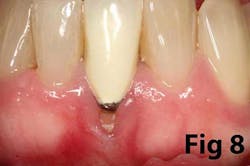

There is an abundance of literature showing increased gingival inflammation around natural dentition (exacerbated when a fixed restoration is present) when there is less than 2 mm AG. (Figs. 8, 9: post grafting) There is an abundance of literature showing increased incidence of peri-implant mucositis when there is inadequate attached tissue — a weaker connective tissue adhesion and lack of Sharpey’s fibers make the peri-implant tissue even more susceptible to bacterial challenge. (1-6, 8, 10) And as periodontitis is always preceded by gingivitis, peri-implantitis will be preceded by peri-implant mucositis. If we can decrease the incidence of peri-implant mucositis by providing a better and more resilient tissue phenotype, we can lower the incidence of peri-implantitis.The FGG procedure is indicated in cases of implant therapy where this is less than 2 mm of attached tissue present. Sometimes, a FGG is preferred over CTG because: (1) the FGG results in greater gain of attached tissue, (2) the FGG alleviates frenum/muscular pull whereas the connective tissue may increase muscular tension after the flap is coronally advanced, and (3) creeping attachment is often a positive byproduct of the FGG procedure.